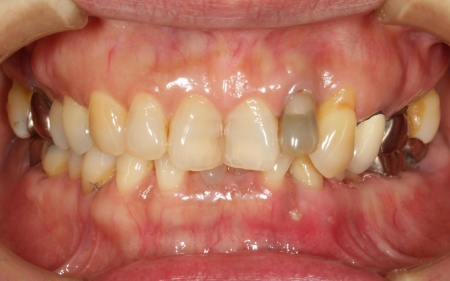

60代女性 変色した前歯に根管治療を施しセラミックの被せ物を装着した症例

拝見したところ、左上の前歯に変色が見られました。この歯は神経が死んでしまった失活歯です。

失活歯とは歯の神経や血管が機能しなくなった歯のことで、神経が失われると歯の内部へ栄養が行き届かなくなるため、時間の経過とともに歯の色が徐々に黒っぽく変化してしまうことがあります。

また、失活歯の内部には細菌に感染した神経の組織が残っている場合があります。このまま放置すると、歯の根の先や周囲の骨へ細菌感染が広がる可能性が考えられました。

レントゲン検査なども行い総合的に確認した結果、まずは歯の内部をしっかりと清掃・消毒する根管治療が必要と診断しました。